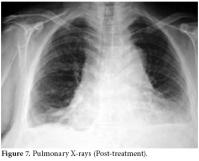

A chest radiograph showed an increased cardiothoracic index and medium to severe bilateral pleural effusion which was more pronounced in the posteroanterior right lung (figure 1).

Pulmonary X-rays showed moderate and severe bilateral pleural effusion, more pronounced in the right lung, and an increased cardiothoracic index.